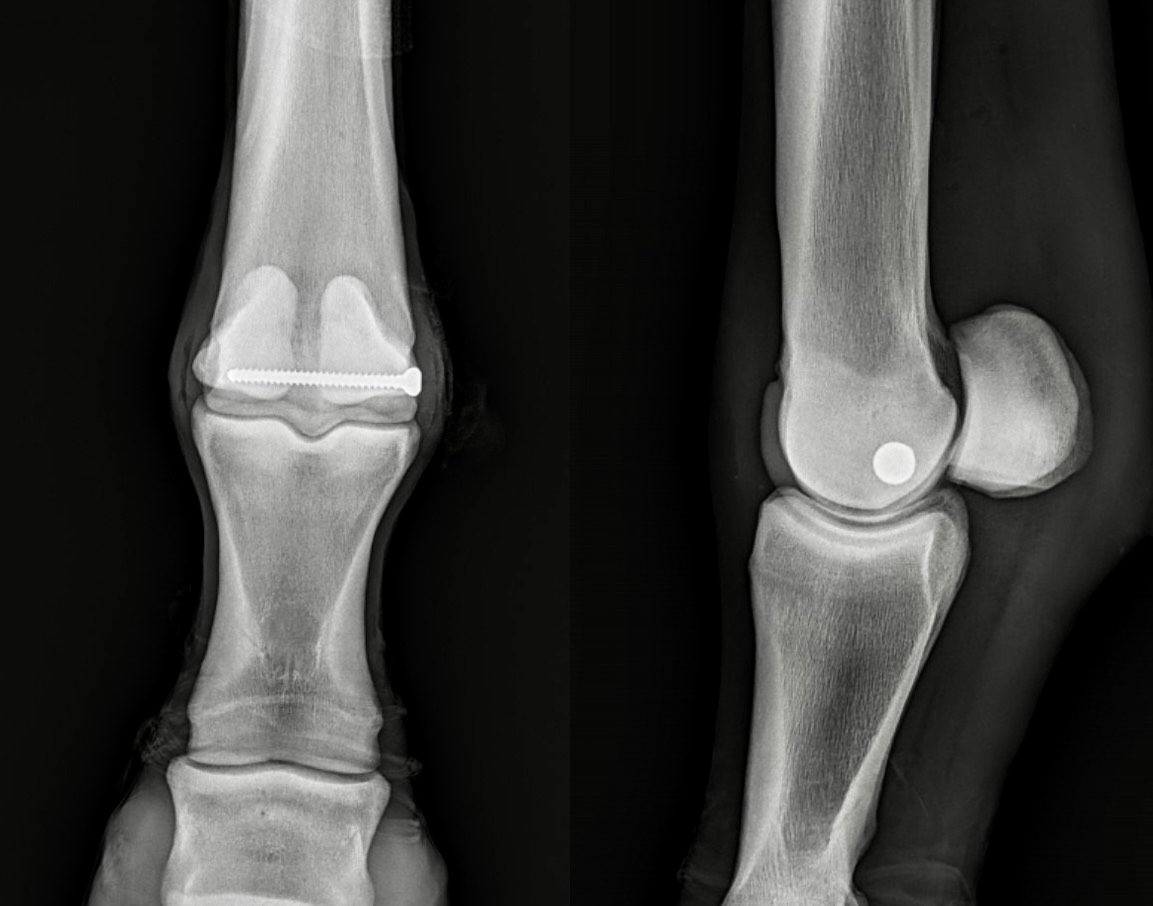

Computed Tomography (CT) is a game-changer for imaging in vet med. CT allowed for precise repair of this very complicated chronic coffin bone (P3) fx thru a tiny hole in the hoof. Using CT mapping w/markers, we could safely place screw as close to joint as possible for best result and see true alignment/proper compression of joint in 3-D 🤓